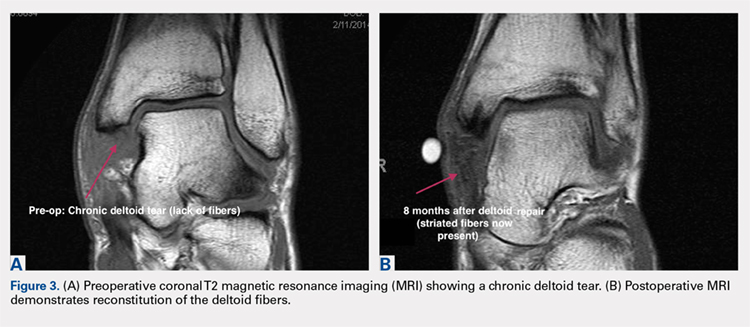

Soccer places an unusually high demand on both the medial foot and ankle structures when compared with other sports. For instance, striking the ball requires the player to abduct and externally rotate the foot, which preloads medial structures.9 Hintermann18 looked at 54 cases of medial ankle instability and found that injury commonly occurred during landing on an uneven surface, which applies to soccer players when landing after heading the ball or jumping over a tackle. Pronation with eversion and extreme rotational injuries are well known to cause deltoid ligament injury. However, complete rupture of the deltoid ligament is rare and is more often associated with ankle fractures.41 Due to its close proximity and similarly shared function in medial plantar arch stabilization with the tibiospring and spring ligaments, posterior tibialis tendon dysfunction is also frequently seen in medial ankle instability.17 After an acute injury, patients can present with a medial ankle hematoma and pain along the deltoid ligament. Although chronic insufficiency is diagnosed based on the feeling of “giving way,” pain in the medial gutter of the ankle and a valgus and pronation deformity of the foot can be corrected by activating the peroneus tertius muscle. Arthroscopy is the most specific way to confirm clinically suspected instability of the medial ankle; however, MRI can demonstrate loss of organized medial fibers (Figures 3A, 3B).18 Primary surgical repair of deltoid ligament tears yield good to excellent results and should be considered in the soccer player to prevent problems associated with chronic non-repaired tears such as instability, osteoarthritis, and impingement syndromes.18 After surgical repair, players will undergo extensive physical therapy that progresses to sport-specific exercises with the ultimate goal of returning to competitive play around 4-6 months post-operatively.